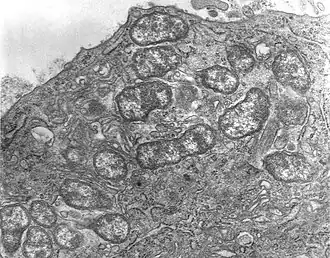

Micrographie électronique à transmission (TEM) montrant une cellule mésothéliale péritonéale d'une souris infectée expérimentalement par voie intrapéritonéale par Orientia tsutsugamushi. On voit plusieurs spécimens circulant librement dans le cytoplasme de la cellule mésothéliale.